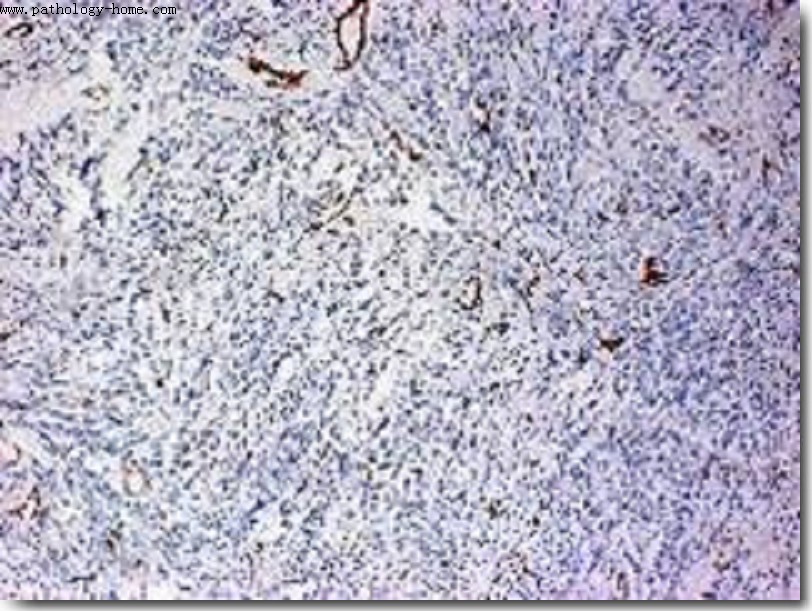

6.病理检测:HE染色、特殊染色、组织切片、免疫组化、流式细胞分选